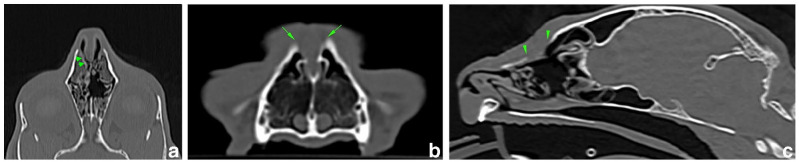

病例摘要:一只 6 岁的雌性绝育短毛猫在 7 个月前出现鼻背皮下肿块。CT 检查显示该猫存在鼻腔皮样窦囊肿和鼻骨缺损。手术切除了囊肿,并采用自体筋膜移植进行重建。鼻背骨得到了重建,长期结果显示呼吸功能没有受到影响。两周随访时未发现短期并发症。在 2 个月和 12 个月的随访中未发现长期并发症或复发。在猫鼻腔皮样窦囊肿手术切除后,筋膜移植似乎是修复鼻骨缺损的有效方法。这种方法成本低廉,组织易于采集,并能提供良好的功能和外观效果:据作者所知,这是第一份评估使用自体筋膜移植修复猫鼻皮样窦囊肿切除术后鼻骨缺损效果的报告。

Case summary: A 6-year-old female spayed domestic shorthair cat was presented with a 7-month history of a subcutaneous mass on the dorsal nasal surface. A CT examination revealed the presence of a nasal dermoid sinus cyst with a nasal bone defect. The cyst was excised and an autologous fascia lata graft was used for reconstruction. The dorsal nasal bone was reconstituted and no compromise of respiratory function was reported in the long-term outcome. No short-term complications were observed at the 2-week follow-up. No long-term complications or recurrence were observed at the 2- and 12-month follow-ups. Fascia lata grafting appears to be an effective method for repairing a nasal bone defect after surgical excision of a nasal dermoid sinus cyst in cats. It is inexpensive and the tissue is easily harvested and provides good functional and cosmetic results.

Relevance and novel information: To the authors' knowledge, this is the first report that evaluates the effectiveness of repairing a nasal bone defect after dermoid sinus cyst excision in a cat using an autologous fascia lata graft.